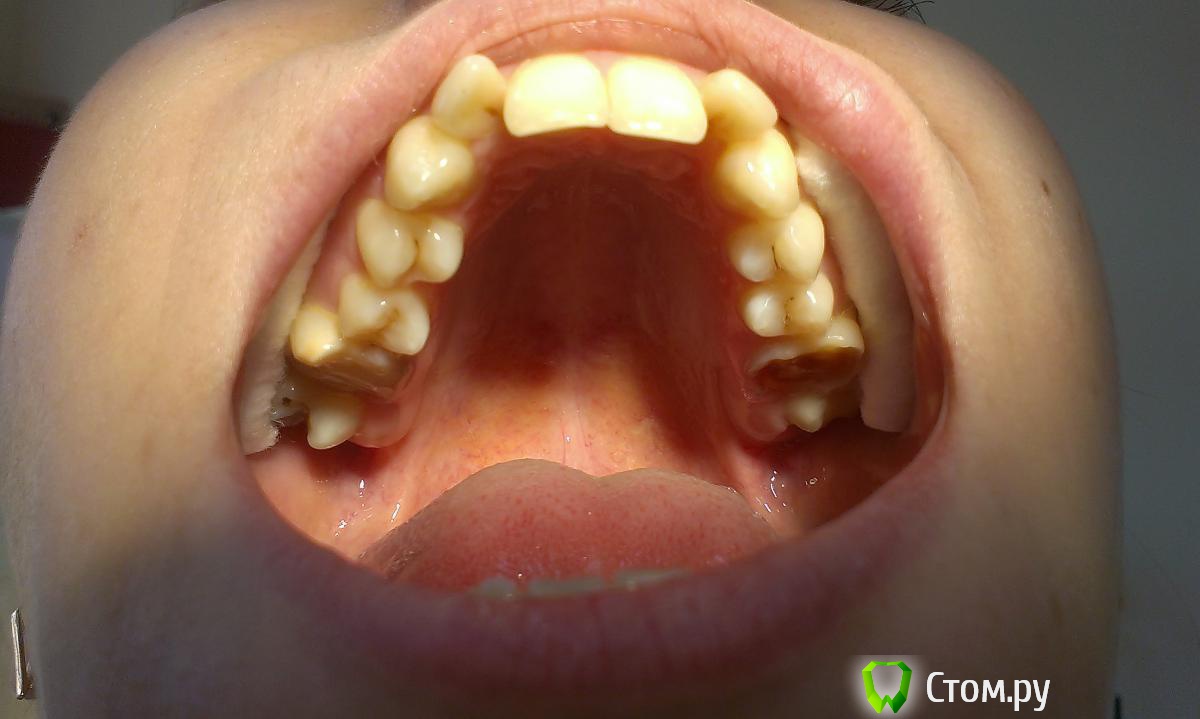

innessa Опубликовано 23 апреля, 2014 Поделиться Опубликовано 23 апреля, 2014 Здравствуйте. Ищу помощи и возможности принять правильное решение в лице стом.ру. Моя ситуация такова: мне 23 года, 1 год и 4 мес. прошло с тех пор, как мне установили брекет систему на нижнюю челюсть, перед этим удалив нижние шестые зубы. На ОПТГ картина 1 мес. назад.мой доктор-ортодонт рекомендует мне теперь удалить верхние четвертые зубы и продолжать ортодонтическое лечение.Что меня беспокоит, четвертые зубы абсолютно здоровы, в отличии от шестых и седьмых ( верхняя челюсть); была на консульт. и у других специалистов этой отрасли- у каждого свое мнение по поводу дальнейшего плана лечения и все они разные. помогите принять верное решение! Ссылка на комментарий

innessa Опубликовано 24 апреля, 2014 Автор Поделиться Опубликовано 24 апреля, 2014 снимки Ссылка на комментарий